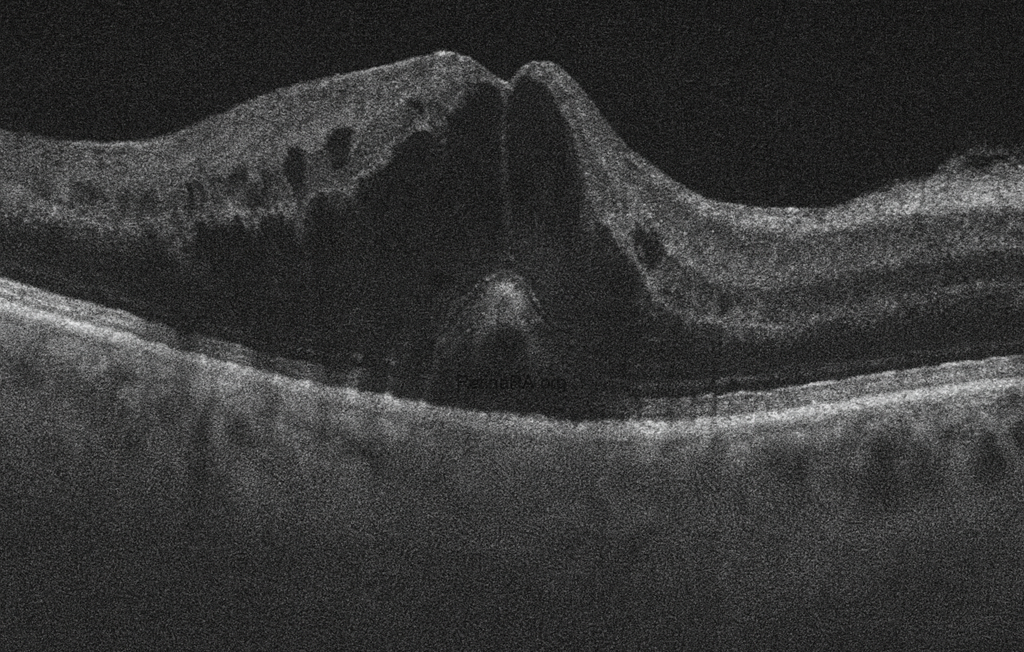

The optical coherence tomography (OCT) image shows significant macular edema with marked retinal thickening. Multiple intraretinal hyporeflective cystoid spaces are present, consistent with cystoid macular edema. There is also a dome-shaped elevation at the fovea, suggesting serous detachment of the neurosensory retina. The normal foveal contour is lost, and the retinal architecture appears markedly disorganized. Hyperreflective foci are scattered within the retina, likely representing hemorrhagic or exudative material. These findings are characteristic of macular involvement in central retinal vein occlusion.